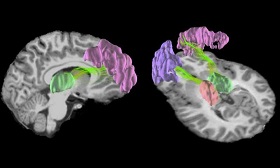

محققان با استفاده از یک نوع جدید از ام.آر.آی به نام "diffusion kurtosis imaging" برای بررسی عصب پیچیدهای که ماده خاکستری را تشکیل میدهند، استفاده کردند. آنها دریافتند که سازماندهی ماده خاکستری در مغز بازیکنان پس از یک سال فوتبال بازی کردن، تغییر کرده است.

پژوهشگران قصد داشتند تا دریابند آیا ضربات مکرر به سر نیز میتواند ماده خاکستری مغز را تحت تاثیر قرار دهد یا خیر. پس از انجام مطالعات آنها دریافتند ماده خاکستری در ناحیه قشر خارجی مغز واقع شده است، بنابراین اگر ضربهای به مغز وارد شود، به طور مستقیم بر این ناحیه تاثیر میگذارد.

پس از اسکن، پژوهشگران متوجه تغییرات قابل ملاحظه ای در ساختار ماده خاکستری در جلو و عقب مغز شدند.

آنها دریافتند تاثیرات بسیاری در ساختار ماده خاکستری و همچنین ساختار عمیق داخل مغز رخ داده است.